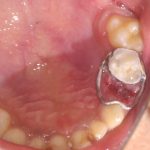

We at the Department of Pediatric & Preventive Dentistry focus on comprehensive oral health care needs of a child from infancy to adulthood and provide comprehensive, therapeutic as well as preventive care to all children including those with special care needs.

Treatment and Services